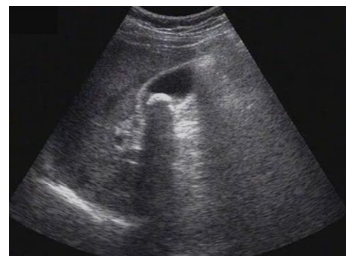

試題3:患者女性,50歲,間斷上腹隱痛半年,診斷為(2分)

【答案】C